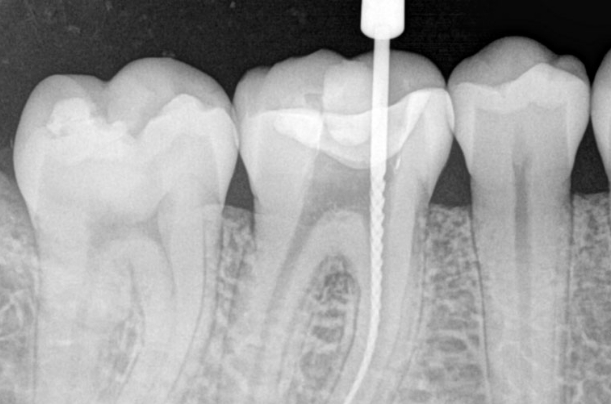

Root Canal Therapy Step by Step

What To Expect When Having A Root Canal in Mexico?